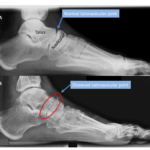

저작권[doctormodu]1 talonavicular arthritis x-ray

05 거주상골 관절염 Talonavicular Arthritis